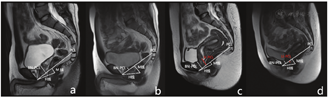

(7)耻骨前列腺角(puboprostatic angle,PPA):正中矢状位T2WI图像上耻骨联合与膀胱颈轴线之间的夹角(图3a、图3b)。

a、b:男性,28岁,静态PPA约55.16°,动态最大力排相PPA增加至约67.24°

a, b: Male, 28 years old, static PPA was about 55.16°, dynamic maximum force phase PPA increased to about 67.24 °